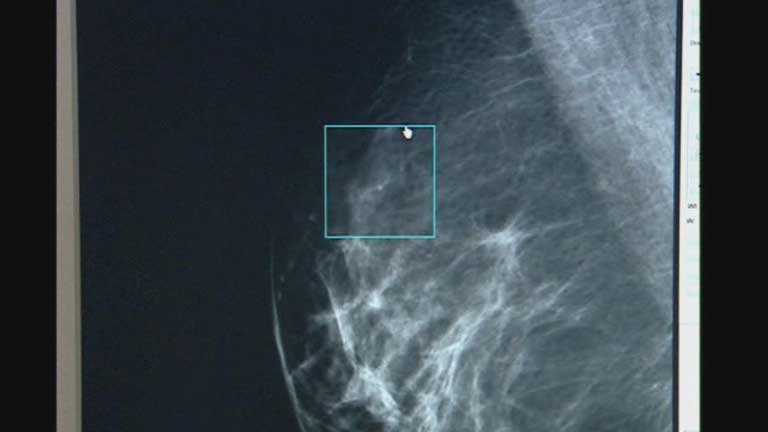

Investigadores del hospital Vall d'Hebron de Barcelona han encontrado un método para mejorar el diagnóstico de los tumores de mama más frecuentes. El nuevo sistema ayuda a perfeccionar el tratamiento y podría evitar en algunos casos la quimioterapia.